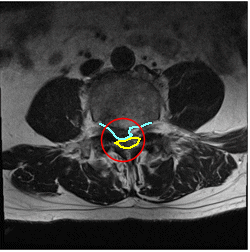

腰の骨ヘルニアのMRI画像 MRI画像

13日目、

MRIの結果を持って、整形外科で見ると、腰椎4番、5番の椎間板ヘルニアが、見られました。

大きな突出で、それも中央に近く、精神的ショックを受けました。

右足だけでなく左足もしびれていてもおかしくない状態でした。

ドクターから、opするなら紹介しますと言われましたが

改善傾向がみられるので、このまま運動療法を続けて改善しないときは、お願いしますと帰宅しました。